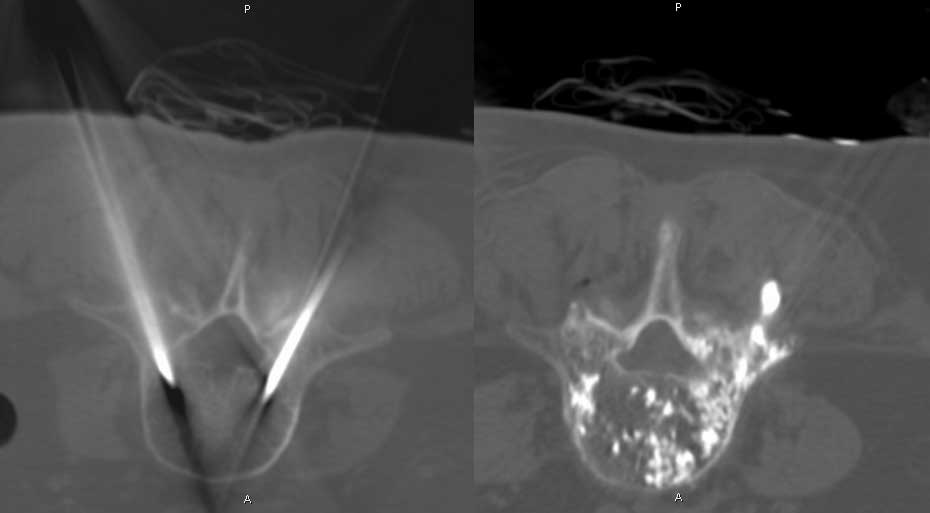

CT - důležité při postižení axiálního (osového) skeletu, stanovení stability, porušení kontinuity zadních elementů páteře

Cementoplastika - do osteolytické léze je perkutánní technikou aplikován kostní cement. Kontraindikací je vyplnění léze, která zasahuje do kloubu nebo intervertebrálního disku.

Cementoplastika může výhodně navazovat na předcházející RFA - provedení stabilizace osteolytické léze.

Vertebroplastika - podstatou metody je vyplnění obratlového těla (infiltrace) speciálním kostním cementem.

Kyphoplastika - metoda je obdobná jako vertebroplastika, ale před aplikací kostního cementu je pomocí speciálního nástroje vytvořená kavita (dutinka) v obratlovém těle nebo v osteolytickém ložisku. Tím může dojít k reparaci výšky obratlového těla. Při zavedení do osteolytické léze tato provedená komprese vytvoří tlakový uzávěr odvodných žil. Druhou výhodou je, že aplikovaný kostní cement není tekutý, má konzistenci "žvýkací gumy", a proto jen minimálně může dojít k úniku kostního cementu mimo oblast zájmu.